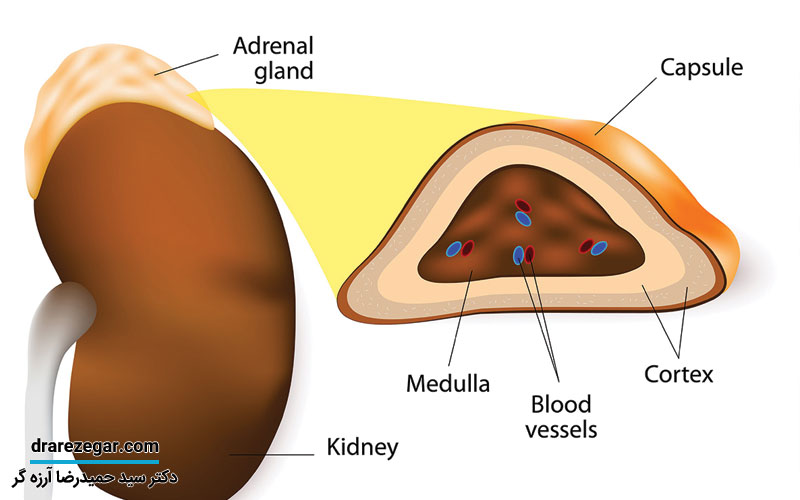

در اصطلاح پزشکی به غدد فوق کلیوی، غدد آدرنال گفته می شود که به صورت دو غده درون ریز بوده و هر کدام روی کلیه قرار می گیرد. وزن تقریبی هر کدام از این غده ها ۵ گرم است و به ۲ بخش قشر و مغز یا مدولا تقسیم می شوند. لازم به ذکر است که هر کدام از این دو بخش می توانند یکسری هورمون های متفاوت ترشح کنند.

بخش قشر غده آدرنال نسبت به مدولای آن اهمیت بیشتری دارد. به طوری که اگر این بخش برداشته شود فرد می میرد. در حالی که اگر بخش مدولا برداشته یا تخریب شود، فقط یکسری اختلالات برای فرد به وجود می آید. دسته ای از هورمون ها با نام کورتیکواستروئید توسط قشر غده آدرنال تولید می شوند. در واقع ۳ لایه داخل قشر آدرنال وجود دارد که این لایه ها به ترتیب از خارج به داخل شامل گلومرولا، فاسیکولا، رتیکولا هستند.